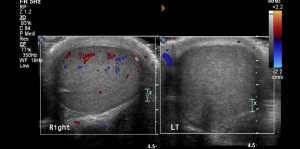

Allison Tadros/WVU Department of Radiology CC BY-SA 4.0